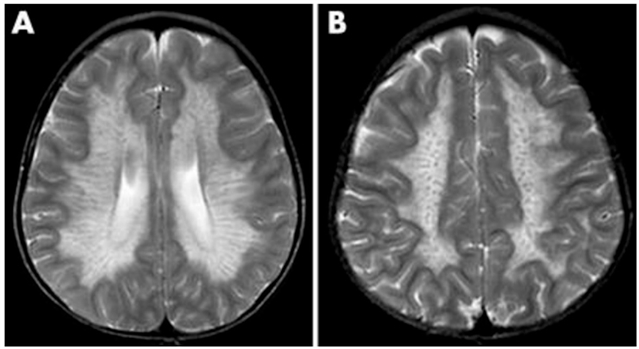

2. 异染性脑白质营养不良

常染色体隐性遗传,芳基硫酸酯酶 A 缺乏导致硫苷脂蓄积。

• MRI 特征:早期脑室周围白质对称性脱髓鞘,进展后出现特征性 **“虎纹征” 与 “豹纹征”**,胼胝体压部受累为典型标志。

• 辅助检查:芳基硫酸酯酶 A 活性显著降低,尿硫苷脂升高。

异染性脑白质营养不良的 MRI 表现(A)呈低信号放射状条纹,类似虎皮外观(虎纹征)。(B)呈低信号点状改变,类似豹皮外观(豹纹征)。